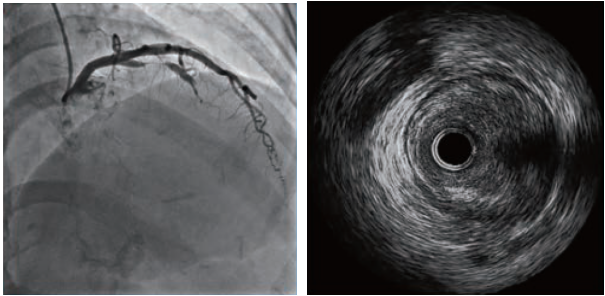

重度狭窄典型图像

病变特点

IVUS 通过对病变程度、性质和累及范围的精确判断,可帮助选择治疗策略和方法,指导介入治疗过程,实现经皮冠状动脉介入治疗术后即刻支架最优化,并可监测相关并发症。

早期研究提示,对于非左主干包括前降支、回旋支和右冠状动脉及其主要分支近段病变,重度狭窄(介人治疗的 IVUS 界限值)为面积狭窄>70%、最小管腔直径<1.8 mm 、 MLA <4.0mm2。

近年来的荟萃分析结果显示,对非左主干、参考血管直径>3 mm 的病变,介人治疗的 IVUS 界限值为 MLA <2.8mm2;对参考血管直径<3 mm 的病变,介入治疗的 IVUS 界限值为 MLA <2.4mm2。